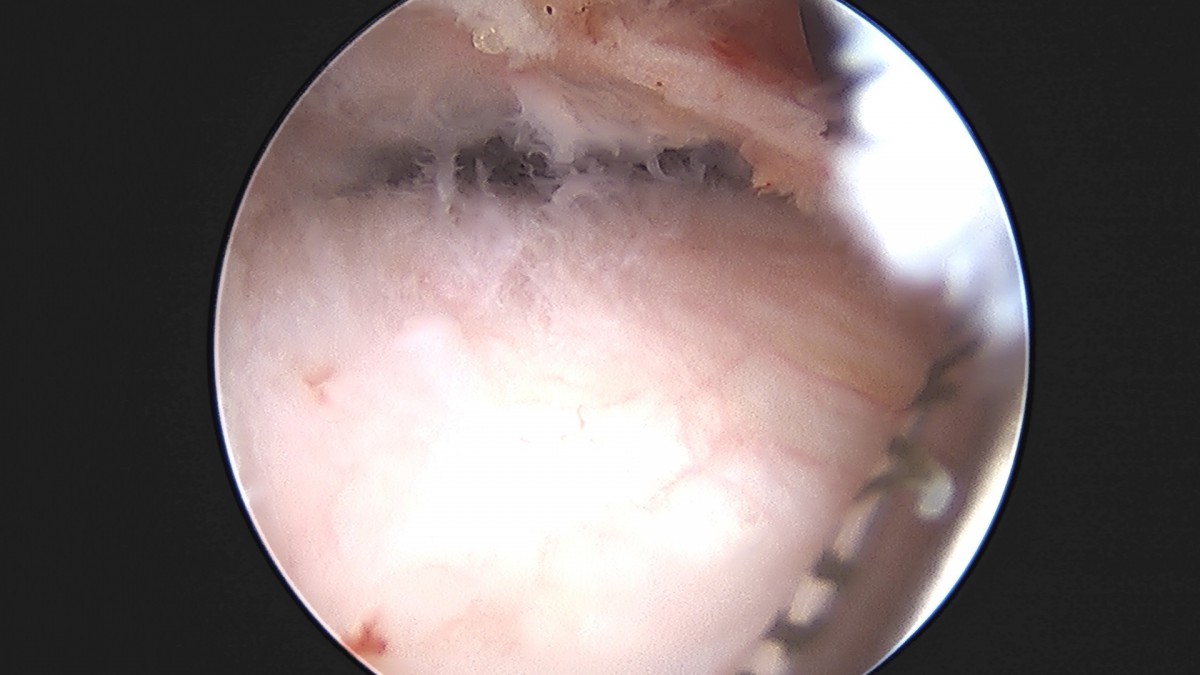

이재상원장님 어깨 견봉하 감압술 이승O 환자

작성자 최고관리자 댓글 0건 조회 806회 작성일 25-09-16 15:26